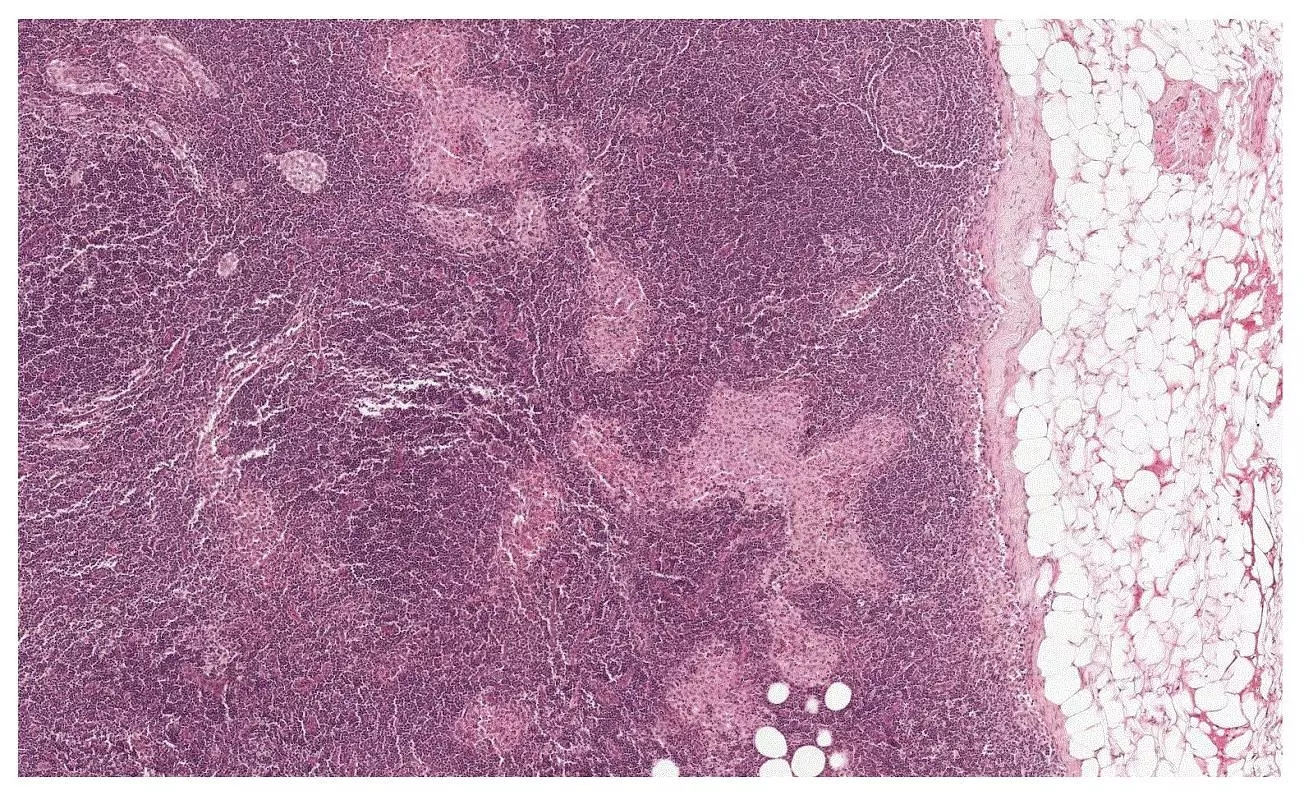

▲你能从这张切片中,找到哪些是肿瘤,哪些是正常组织,哪些是看起来很像肿瘤的正常组织吗?(图片来源:谷歌)然而,这样一个足以影响生命的环节,却有着很大的先天不足。首先,人工诊断很容易出错。许多研究人员发现,即便是对于同一名病人,不同病理学家给出的诊断也往往会有很大不同:一篇2015年的论文发现,不同病理学家对乳腺癌诊断的一致率只有75.3%。在某些异型乳腺癌中,诊断的一致率竟下降到了48%,不足一半。可想而知,不少患者面临着误诊的风险,这也无疑让正在与死神赛跑的患者绕了弯路,使病情雪上加霜。其次,尽管病理学家并非尽善尽美,要培养出这样一名人才却绝非一朝一夕之功。在经过基础的医学院学习后,这些专家必须经过数年的训练,才能掌握足够的经验,学会分析病理切片的技巧。在医疗资源不足的地区,想要得到诊断,都是一种奢望。科学家们表示,这两大先天不足的背后,有着一个共同原因——这些病理学家需要处理的信息太多了。对于单独一名患者来说,这些切片的数量就不止一张,而每一张切片在显微镜下都含有数百亿个像素。这是一个什么样的概念呢?谷歌的一则报道为我们做了一个比方。假设我们有1000张含有数千万像素的高清照片,你要有能力辨别这1000张照片中,哪一个像素可能出了问题。

▲要正确诊断癌症,得要在几百亿个像素里找到出错的那几个(图片来源:KingofWallpapers)对于普通人类来说,这基本上是个不可能完成的任务。更何况,病理学家用来分析切片的时间非常有限。这也就解释了为何要花上几年时间才能训练出一名病理学家,也能解释为何不同病理学家可能会对同一名患者的切片做出不同判断。但对人工智能来说,这不是一个问题。人工智能的奇迹在诸多人工智能中,基于卷积神经网络的系统在图像识别上早已彰显出自身的力量。此前,《自然》封面曾报道了一款能诊断皮肤癌的人工智能,它的特异性和灵敏度甚至超过了人类皮肤科的专家。既然病理切片也能被处理成数码图像,人工智能能否被用来分析切片,并诊断乳腺癌呢?谷歌和Verily的科学家们做了一个尝试。由于单张切片的照片过于庞大,他们将这些图像分割成了数万至数十万个128x128像素的小区域,每个小区域内可能含有数个肿瘤细胞。随后,他们提供了许多肿瘤组织与正常组织的病理切片,供人工智能学习。最终,这款人工智能掌握了一项像素级的技巧——它能分辨出单个小区域内被标注为“肿瘤”的像素,从而将整个小区域标注为“肿瘤区”。这能有效将肿瘤组织与健康组织区分开来。